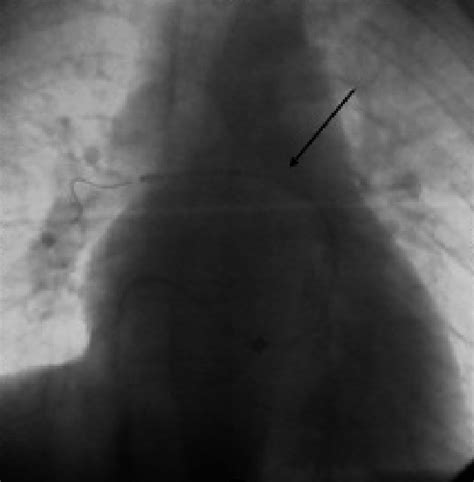

Aspirex device placed on the right pulmonary ar...